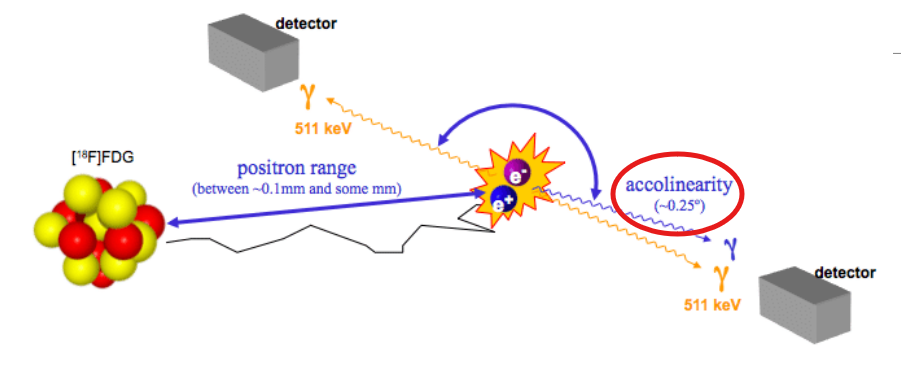

Picks up on the energy emitted from an annihilation interaction between an electron and a positron that’s lost energy – positively charged electron

Is a byproduct of beta positive decay

The parent is unstable and has too many protons → will convert one of the protons into a neutron

As consequence of this conversion, it will create a positron as a byproduct that will get ejected from the nucleus

The positron will travel a length of distance – losing energy until it becomes a positively charged electron

It will then interact with a negatively charged electron and cause an annihilation reaction

Rest mass is what occurs when the positron has traveled a distance and runs out of energy – is now mainly made up of mass

2 photons are emitted – one is equal to 511 keV

1.02 MeV – 511 keV + 511 keV

The positron needs to have reached its rest mass – or else the photons made would be more than 511 keV

What are the 3 types of errors that PET scanners are associated with?

Error associated with the distance that the positron travels before the annihilation occurs – affects the line of response

Non-colinearity or acolinearity

Elaborate on why there is error associated with PET specific to the distance that the positron travels prior to annihilation

When the positron is made as a byproduct of beta positive decay, it’s ejected from the nucleus and will travel a distance away due to it being high in energy

As a PET camera detects annihilation reactions, every line of response it detects will have around 0.1 mm of error from the range of the positron traveling a distance

Elaborate on how non-colinearity or acolinearity is a source of error for PET

Our detectors in a PET camera work to pick up on two 511 keV photons that are traveling at a straight distance from one another

With non-colinearity, one of the photons will travel at a slight angle (0.25°)

Non-colinearity as this is a source of error that occurs at the origin of the annihilation event